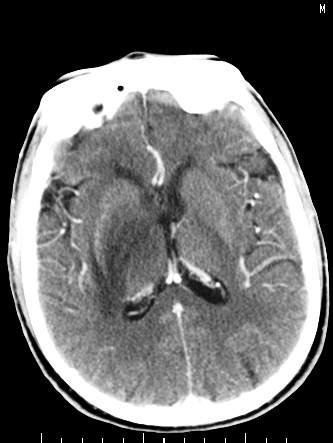

m/50,头昏头痛1月,近3天感觉左半肢体活动不利,自述半年前呈患肺tb,腰穿脑脊液未见特殊改变。现做头颅ct请大家会诊。

结核性脑膜炎,结核瘤,梗塞灶三症并存,提示颅内结核感染可能性大。

脑干占位,考虑转移瘤可能性大,不除外胶质瘤.

考虑为:脑干脓肿;不排除胶质瘤或转移瘤。

右侧基底节区缺血性脑梗塞.脑干区考虑结核.

可考虑结核,患者水肿范围大,囊性病灶边缘密度较高,不考虑胶质母细胞瘤